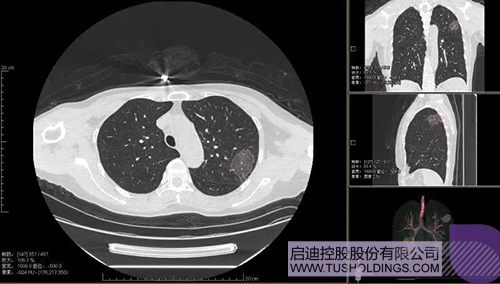

2020年2月11日,啟迪科服投資企業—神州德信推出新冠肺炎檢測及量化智能分析系統,積極助力一線醫務人員科學精準防疫。